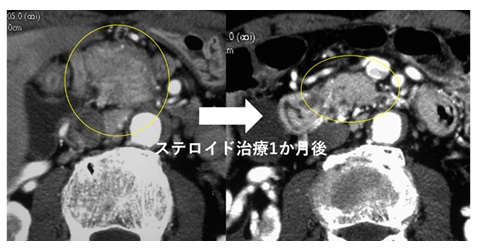

ステロイド薬のひとつであるプレドニゾロンという薬剤を1日30mgで1カ月間内服すると、膵の腫大や膵管の狭細像は明らかに改善します。以後は徐々に減量し最終的に5mg程度で維持することが多いです。 ステロイドを短期で中止にしてしまうと再燃の多いことが知られており、少量のステロイド投与(維持療法)をある程度続ける必要がありますが、どの程度の期間続ければよいかはまだコンセンサスが得られていないのが現状です。

膵頭部腫大の自己免疫性膵炎。ステロイド治療により膵臓が小さくなっている